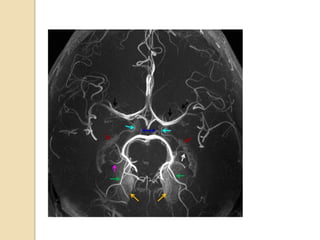

7T 3D CE-MRA

5- Yellow arrow demonstrate

stenosis of-

1- right ICA

2- right vertebral A.

3- right PCOM

4- Right MCA

6- MRA demonstrate

stenosis of -

1- vertebral artery

2- basilar artery

3- PICA

4- AICA

7- MRA demonstrate

Right MCA-

1- Aneurysm

2- AVM

3-Thrombus

4- Hypoplasia

9- Light blue arrow

demonstrate-

1- Anterior choroidal artery

2- Posterior choroidal

artery

3-PCOM

4- PCA

10- white arrow denotes-

1- Anterior choroidal